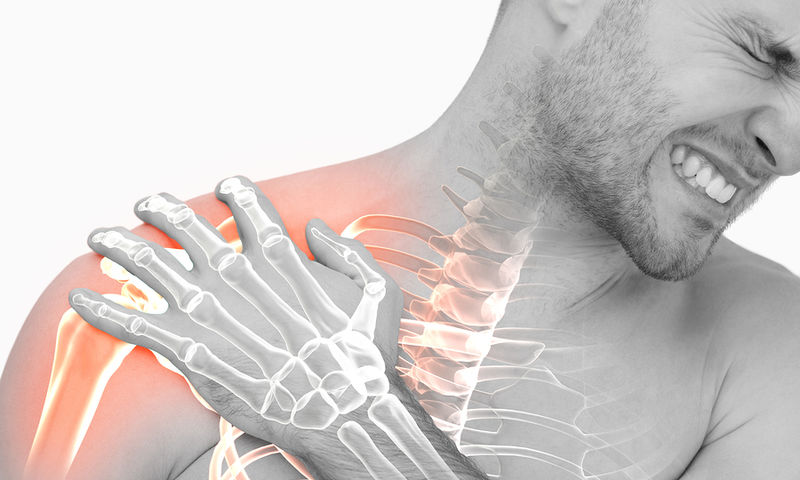

Όταν πονάμε στην μέση της νύχτας, είναι πρακτικώς αδύνατο να κοιμηθούμε.

Αλλά αυτοί οι πόνοι αργά τη νύχτα είναι κάποιες φορές καμπανάκια υγείας που δεν πρέπει να αμελούμε. Σύμφωνα με ειδικούς, ο πόνος τη νύχτα σε ένα συγκεκριμένο σημείο θα μπορούσε να είναι ένα σημάδι ότι πρέπει να ελέγξετε τους πνεύμονές σας για καρκίνο!

Ο πόνος στον ώμο σας όταν ξαπλώνετε μπορεί να είναι σημάδι καρκίνου του πνεύμονα

Ο πόνος στον ώμο μπορεί να προκύψει από πολλές ασθένειες, αλλά ειδικοί προειδοποιούν ότι αν τον παρατηρήσετε τη νύχτα, ή γενικά όταν ξαπλώνετε, μπορεί να σχετίζεται με καρκίνο του πνεύμονα.

Σύμφωνα με το Κέντρο Καρκίνου Moffitt, «εάν ο πόνος στον ώμο εμφανίζεται κατά την ανάπαυση, επιδεινώνεται τη νύχτα ή δεν συνοδεύεται από κάποια απώλεια κίνησης, μπορεί να υποδηλώνει καρκίνο του πνεύμονα».

Αν και ο ώμος είναι κάτι που δεν τον συνδέουμε συνήθως με τους πνεύμονες, ένας όγκος στον πνεύμονα μπορεί να ασκήσει πίεση σε ένα κοντινό νεύρο, με αποτέλεσμα τον πόνο στον ώμο. «Ο πόνος στον ώμο που σχετίζεται με καρκίνο του πνεύμονα σε πρώιμο στάδιο μπορεί να προκύψει από την πίεση του όγκου στα νεύρα», εξηγεί η δρ. Gail Trauco.

Είναι ένα φαινόμενο γνωστό ως αντανακλαστικός πόνος. Είναι δηλαδή πόνος που προέρχεται από ένα μέρος του σώματος αλλά γίνεται αισθητός σε άλλο σημείο. Ένας όγκος του πνεύμονα μπορεί να προκαλέσει πίεση σε ένα νεύρο που περνάει κοντά στους πνεύμονες. Σε αυτήν την περίπτωση, ο εγκέφαλος ερμηνεύει τον πόνο ως προερχόμενο από τον ώμο, ενώ στην πραγματικότητα, το νεύρο που ερεθίζεται είναι μέσα στους πνεύμονες.

Καρκίνος του πνεύμονα: Τι είναι ο όγκος τύπου Pancoast που θα μπορούσε να προκαλέσει πόνο στον ώμο

Ο πόνος στον ώμο είναι ένα ιδιαίτερα σημαντικό σημάδι όταν πρόκειται για όγκο Pancoast. Αυτός είναι ένας σπάνιος τύπος καρκίνου του πνεύμονα που ξεκινά από το στρογγυλεμένο άνω τμήμα του πνεύμονα και εξαπλώνεται σε κοντινές περιοχές του σώματος. Σύμφωνα με έρευνα, που δημοσιεύτηκε διαδικτυακά στο περιοδικό StatPearls, οι όγκοι Pancoast προκαλούν πόνο στους ώμους και τα χέρια σχεδόν σε όλους τους ασθενείς.

Συχνά, οι ασθενείς με αυτήν την μορφή καρκίνου τείνουν να μην αντιμετωπίζουν αναπνευστικά προβλήματα, που είναι κοινά σε άλλους καρκίνους του πνεύμονα. Οι ειδικοί στο Κέντρο Καρκίνου Moffitt λένε ότι άλλα σημάδια ενός όγκου Pancoast περιλαμβάνουν:

- μυϊκή αδυναμία

- μυρμήγκιασμα

- απώλεια αισθήσεων

- έξαψη προσώπου και

- υπερβολική εφίδρωση του προσώπου

Ο πόνος στον ώμο μπορεί επίσης να οφείλεται σε οστικές μεταστάσεις ή σε κακοήθες μεσοθηλίωμα του υπεζωκότα

Ο πόνος στον ώμο μπορεί επίσης να συνδεθεί με οστικές μεταστάσεις, ή με κακοήθες μεσοθηλίωμα του υπεζωκότα. Οι μεταστάσεις των οστών περιλαμβάνουν καρκίνο που έχει εξαπλωθεί στα οστά, σε αυτήν την περίπτωση κοντά στον ώμο.

Περίπου το 30-40% των ατόμων με καρκίνο του πνεύμονα αναπτύσσουν μεταστάσεις στα οστά κάποια στιγμή κατά τη διάρκεια της νόσου τους.

Το κακόηθες μεσοθηλίωμα του υπεζωκότα είναι ένας καρκίνος των μεμβρανών που καλύπτουν τους πνεύμονες και συχνότερα σχετίζεται με την έκθεση στον αμίαντο. Το 14% των ασθενών αναφέρει τον πόνο στον ώμο στα πρώτα συμπτώματα μεσοθηλιώματος.

Καρκίνος του πνεύμονα: Ο βήχας, η κόπωση και οι πρησμένοι λεμφαδένες είναι μερικά άλλα πρώτα σημάδια

Ο πόνος στον ώμο δεν είναι το μοναδικό πρώιμο σημάδι καρκίνου του πνεύμονα. Η δρ. Trauco λέει ότι άλλα πιθανά συμπτώματα είναι:

- ανεξήγητη απώλεια βάρους

- υπερβολική κόπωση

- δύσπνοια

- βήχας που δεν υποχωρεί

- βήχας με αίμα

- πρήξιμο των λεμφαδένων και

- ανεξήγητο πρήξιμο των άνω άκρων